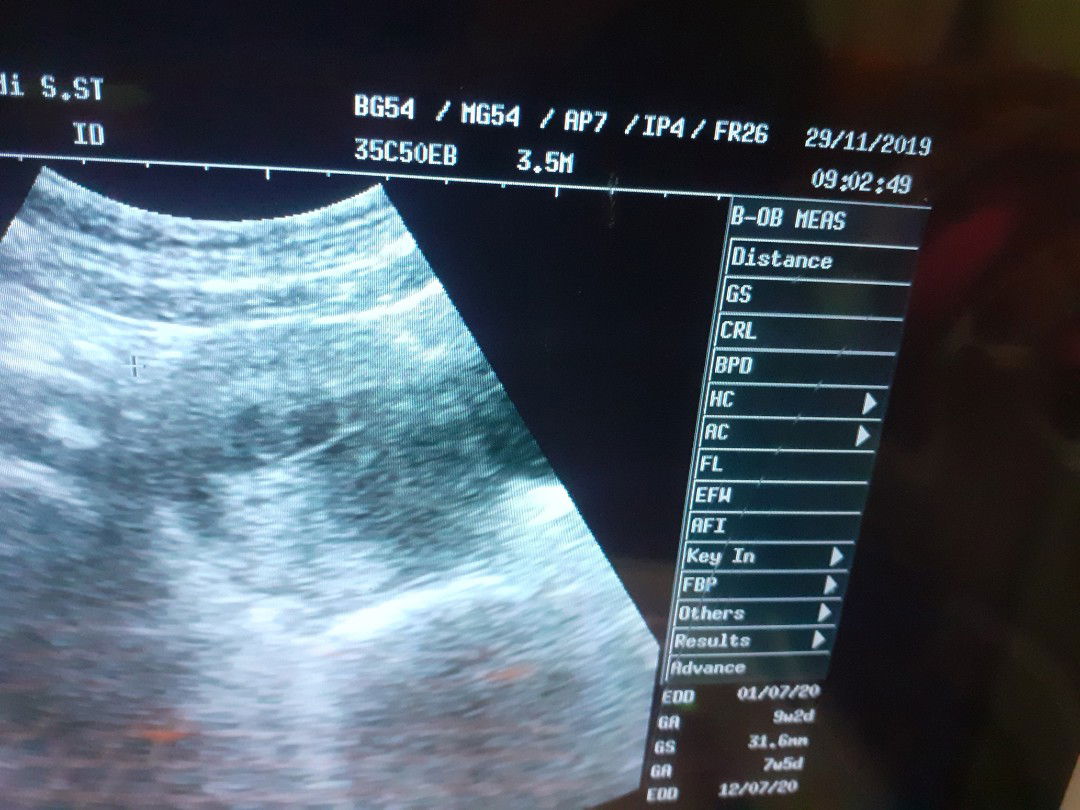

Bunn..emang uk 9w2d GS nya 31,6mm ya?normal gk?takut slah uk nya,soalnya emg beda2,,di puskes 4w5d,dibidan satu udh mau 3 bln agak dekat sh sma yg difoto,di satu lgi segitu,, agak bingung inii mna yg bner Yg mau jwb terimakasihh

Yg benar yg hasil USG Bun